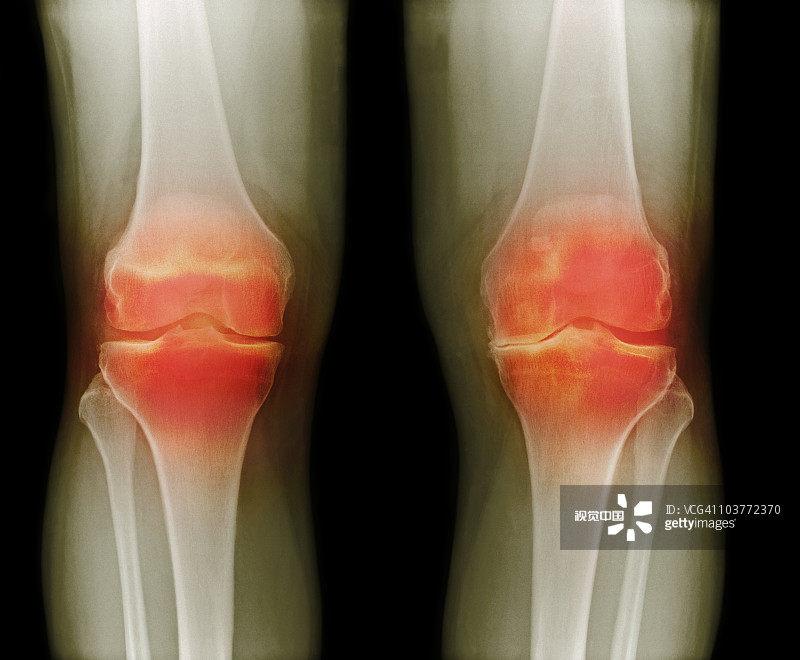

適應(yīng)癥:膝骨關(guān)節(jié)炎

貴醫(yī)附院 | 人臍帶間充質(zhì)干細(xì)胞治療膝骨關(guān)節(jié)炎患者的1期臨床試驗(yàn)